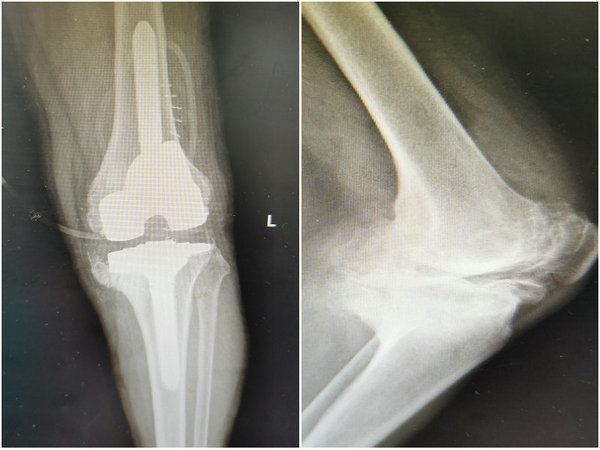

患者术前X线片